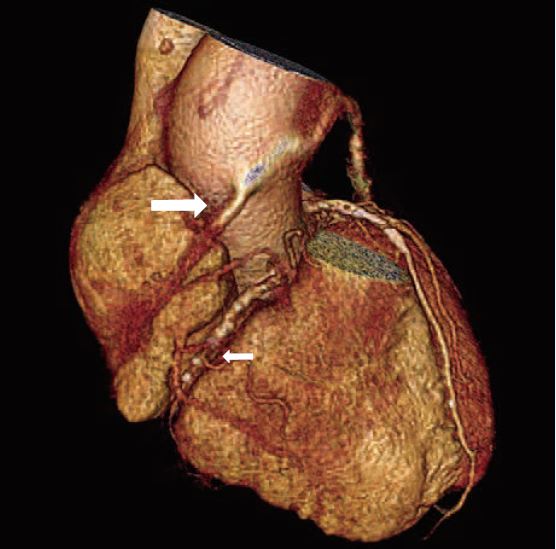

目前CCTA以評估冠狀動脈狹窄為主,但在心臟解剖的正常與否、心肌厚度及引起狹窄的斑塊性質分析也有很大的貢獻。對於曾接受冠狀動脈支架置放術,或是繞道手術的患者,也可有相當不錯的追蹤效果(圖3及圖4)。正在發展中的心肌血流灌注及血流儲備分數(FFR)也愈來愈成熟,指日可待。

圖4:63歲男性,冠狀動脈繞道植管術後。2006年64切CCTA,右冠狀動脈植管近端殘幹仍可見,但中段以下完全阻塞。(大箭號為植管殘幹,小箭號為原生右冠狀動脈阻塞處)